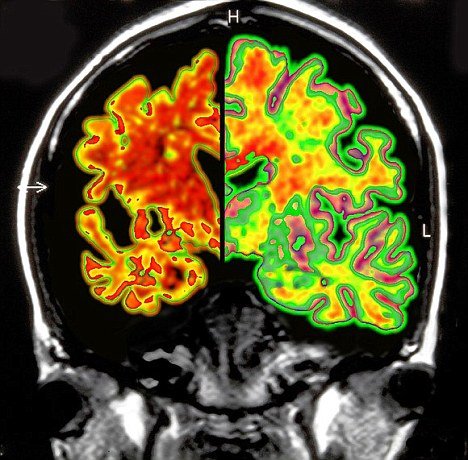

Tag: causes of dementia